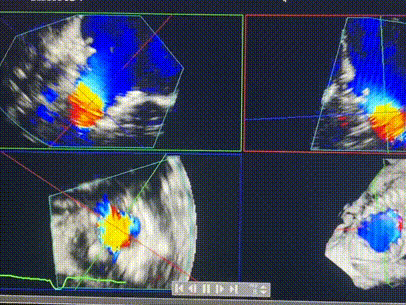

術(shù)后超聲顯示僅殘余微量瓣周漏

LuX-Valve Plus經(jīng)血管三尖瓣置換系統(tǒng)此次“出海”圓滿完成,術(shù)后Rodrigo Estévez-Loureiro教授對(duì)LuX-Valve Plus經(jīng)血管三尖瓣置換系統(tǒng)的器械性能和治療效果大為稱贊,認(rèn)為L(zhǎng)uX-Valve Plus的手術(shù)體驗(yàn)非常好。術(shù)后即刻超聲顯示三尖瓣反流幾乎完全消失,血流動(dòng)力學(xué)改善顯著,患者恢復(fù)快。在面對(duì)復(fù)雜解剖結(jié)構(gòu)、超聲影像質(zhì)量不佳、有起搏導(dǎo)線干擾時(shí),Lux-Valve Plus也體現(xiàn)了極強(qiáng)的適應(yīng)性。Thomas Modine教授和Anson Cheung教授也肯定了LuX-Valve Plus術(shù)中操作的便捷性,認(rèn)為L(zhǎng)uX-Valve Plus容錯(cuò)率高,對(duì)術(shù)中影像的依賴較小,后期希望可以更多的應(yīng)用LuX-Valve Plus三尖瓣置換系統(tǒng)于臨床實(shí)踐,讓更多的三尖瓣重度反流患者盡早獲益,改善預(yù)后。